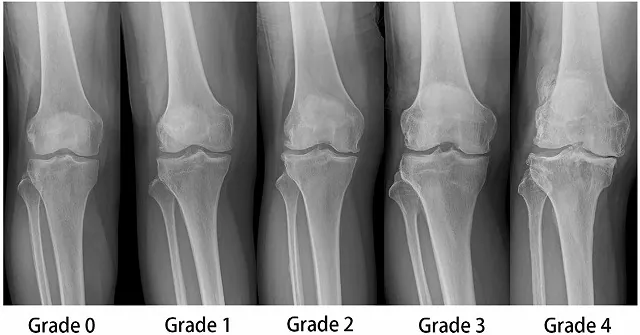

変形性膝関節症の診断方法

診断には患者さんの病歴・年齢・診察所見・画像検査などの情報で判断していきます。画像検査はレントゲン撮影が一般的で軟骨のすり減りの程度や関節の変形の程度を評価していきます。変形性膝関節症の場合、軟骨の摩耗の程度や、骨棘(こつきょく)と言って本来は骨がない場所に骨ができてくるなどの所見があります。

レントゲンで評価が難しい場合や別の疾患との判断が難しい場合はMRIによる検査で、軟骨・半月板・靱帯などの評価を行う場合もあります。